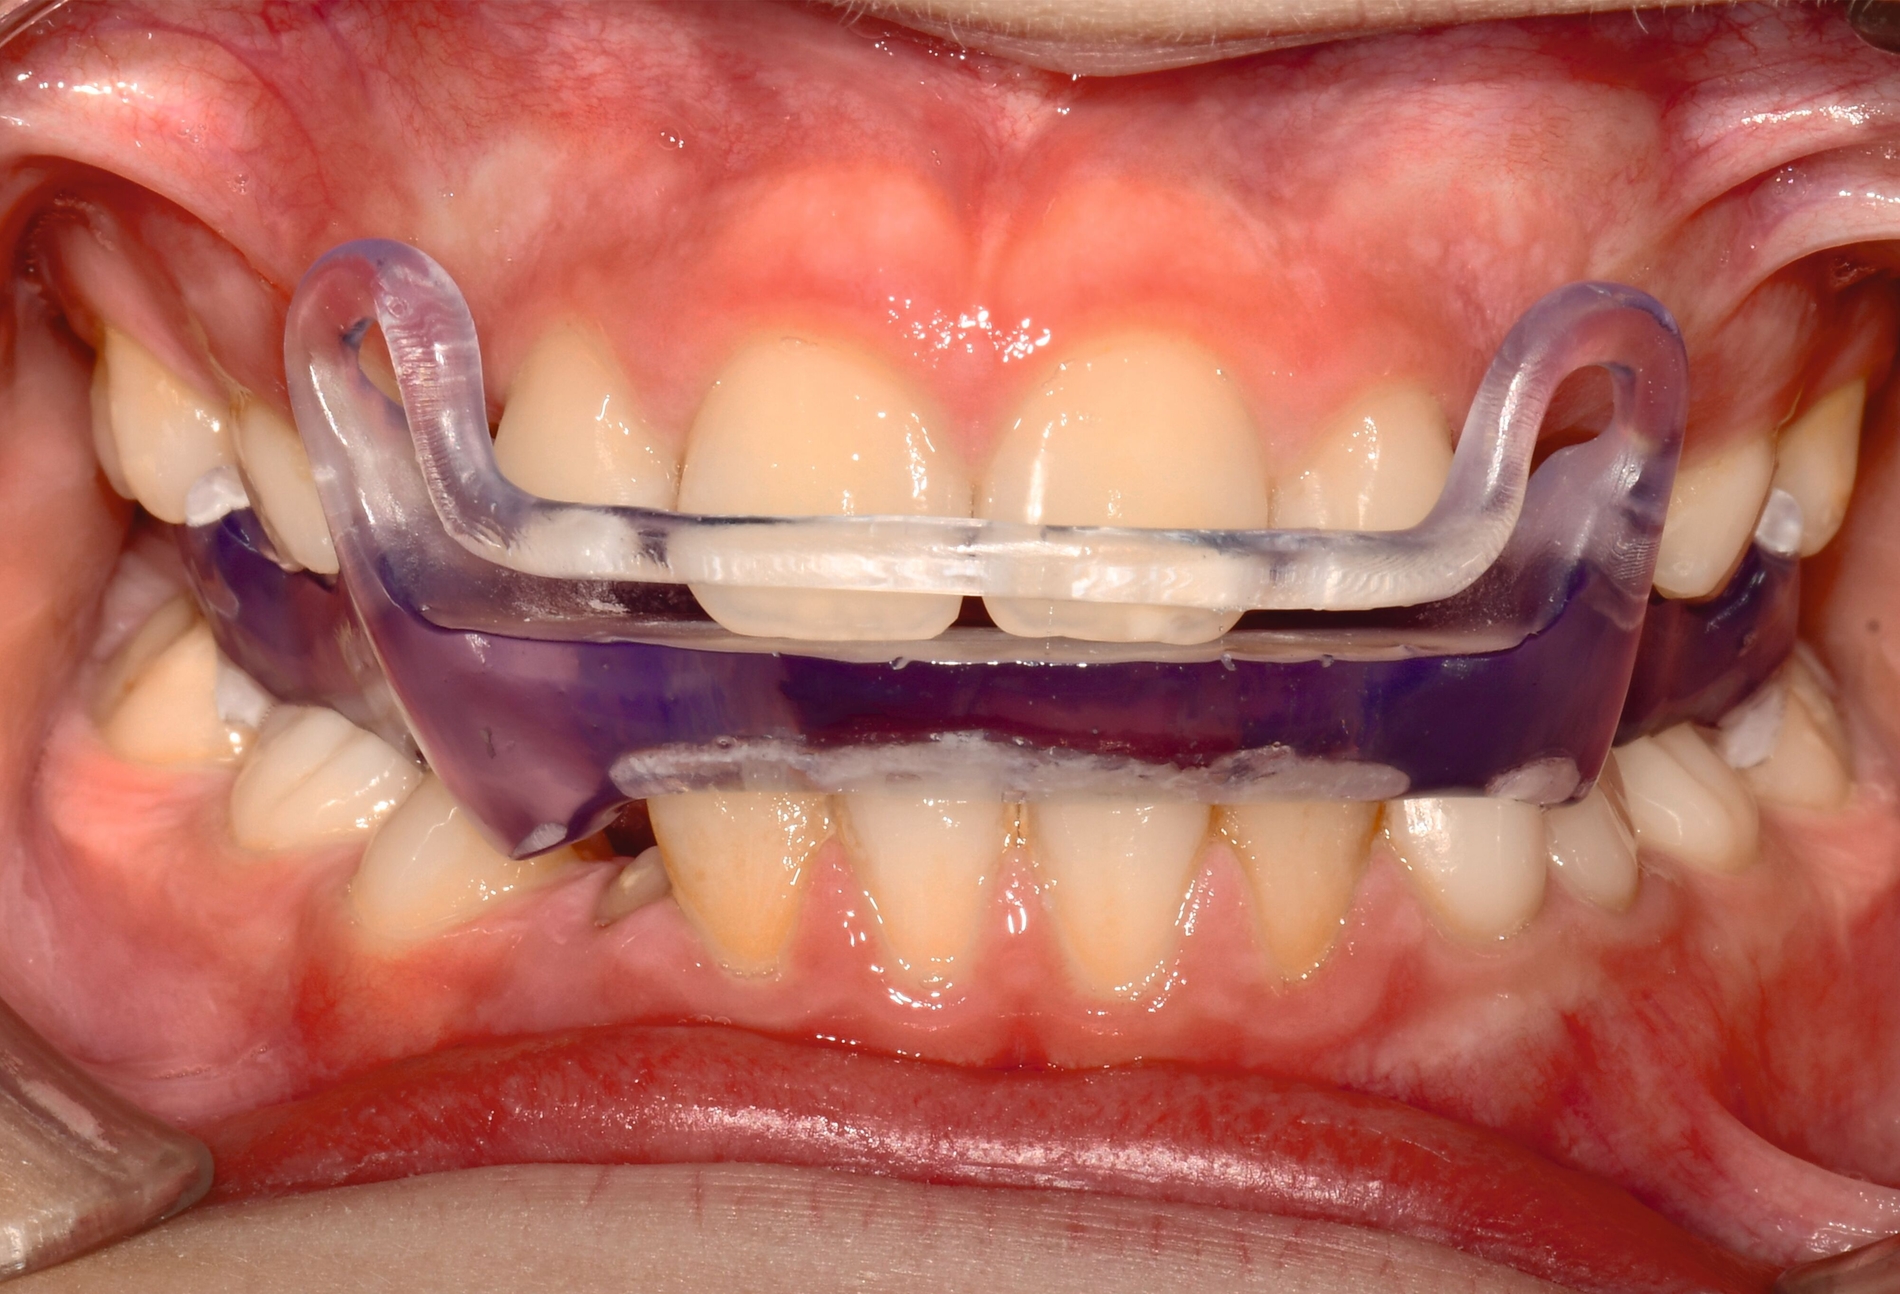

Aligner

Unter den digital gefertigten kieferorthopädischen Apparaturen sind Aligner wohl das bekannteste Beispiel [Ercoli et al., 2014, Robertson et al., 2020]. Die Herstellung von Alignern selbst basiert(e) jedoch auf einer manuellen Fertigung anhand 3-D-gedruckter Modelle und stellt(e) somit bisher eher eine partiell automatisierte Fertigung dar. Die neuesten Entwicklungen erlauben mittlerweile eine Fertigung im direkten 3-D-Druckverfahren [Tartaglia et al., 2021], so dass mühsame, zeitaufwendige Zwischenschritte der manuellen Fertigung entfallen (Abbildung 1a). Weiter profitieren die Patienten von individuelleren Fertigungsmöglichkeiten, da durch die Umsetzung im 3-D-Druck zusätzliche Elemente einfacher und stabiler in den Aligner inkorporiert werden können (Abbildung 1b).